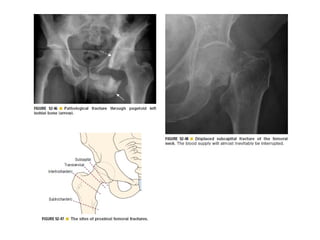

Skeletal trauma was presented by Dr Laith Fadhel with reference to Grainger's Diagnostic Radiology textbook. The presentation covered skeletal trauma as assessed through diagnostic radiology techniques. Key findings and treatments for skeletal injuries were likely discussed.